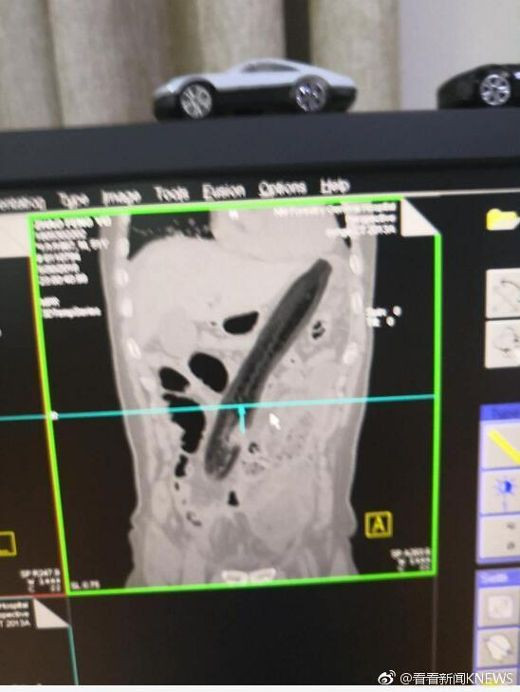

Kết quả chụp X-quang cho thấy quả cà tím quá lớn và bị đẩy lên tận phía trên làm tổn thương phổi của ông ấy.

Bác sỹ đã rút "vật thể lạ" ra ngoài và đo được nó dài khoảng 30cm.

Người đàn ông nhét quả cà tím dài 30cm vào hậu môn để chữa táo bón ảnh 2(Nguồn: Shanghaiist)